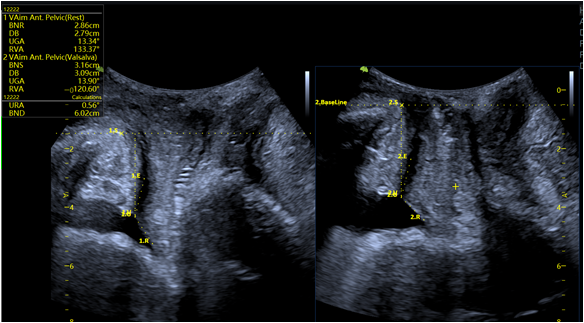

- VAim Pelvic: KI-gestützte Vermessung des Beckenboden